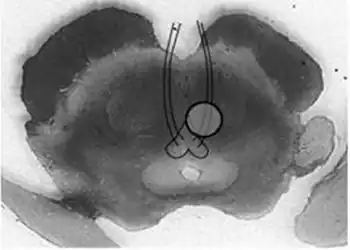

Benedikt syndrome. Localization of oculomotor fascicle injury and symptoms of Benedkit syndrome.

It is characterized by the presence of an oculomotor nerve (CN III) palsy and cerebellar ataxia including tremor and involuntary choreoathetotic movements. Neuroanatomical structures affected include the oculomotor nucleus, red nucleus, corticospinal tracts and superior cerebellar peduncle decussation. It has a similar cause, morphology, signs and symptoms to Weber's syndrome; the main difference between the two being that Weber's is more associated with hemiplegia (i.e. paralysis), and Benedikt's with hemiataxia (i.e. disturbed coordination of movements). It is also similar to Claude's syndrome, but is distinguishable in that Benedikt's has more predominant tremor and choreoathetotic movements while Claude's is more marked by the ataxia.

Benedikt syndrome is caused by a lesion (infarction, hemorrhage, tumor, or tuberculosis) in the tegmentum of the midbrain and cerebellum. Specifically, the median zone is impaired. It can result from occlusion of the posterior cerebral artery[1] or paramedian penetrating branches of the basilar artery.[2]